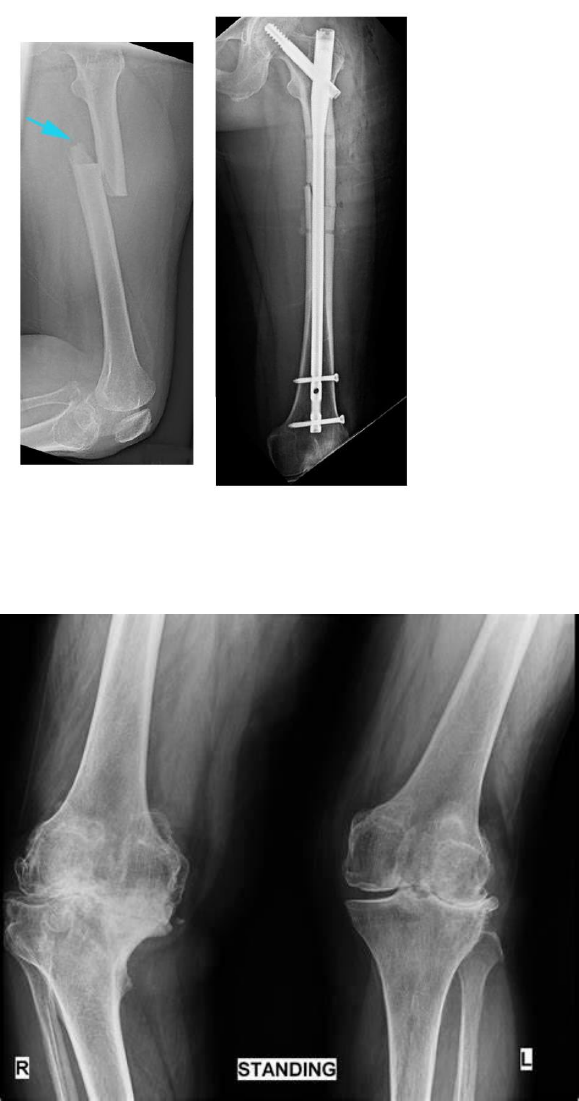

4- De acordo com o exame de imagem abaixo, qual o diagnóstico? Justifique sua resposta.

5- Qual o diagnóstico? Especifique a região afetada.

6- Qual o diagnóstico?